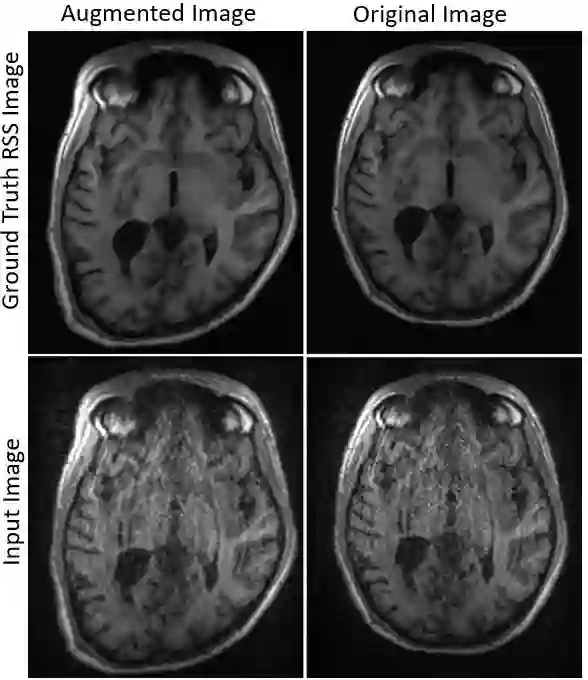

Magnetic Resonance Imaging (MRI) is a non-invasive diagnostic and radiotherapy (RT) planning tool, offering detailed insights into the anatomy of the human body. The extensive scan time is stressful for patients, who must remain motionless in a prolonged imaging procedure that prioritizes reduction of imaging artifacts. This is challenging for pediatric patients who may require measures for managing voluntary motions such as anesthesia. Several computational approaches reduce scan time (fast MRI), by recording fewer measurements and digitally recovering full information via post-acquisition reconstruction. However, most fast MRI approaches were developed for diagnostic imaging, without addressing reconstruction challenges specific to RT planning. In this work, we developed a deep learning-based method (DeepMRIRec) for MRI reconstruction from undersampled data acquired with RT-specific receiver coil arrangements. We evaluated our method against fully sampled data of T1-weighted MR images acquired from 73 children with brain tumors/surgical beds using loop and posterior coils (12 channels), with and without applying virtual compression of coil elements. DeepMRIRec reduced scanning time by a factor of four producing a structural similarity score surpassing the evaluated state-of-the-art method (0.960 vs 0.896), thereby demonstrating its potential for accelerating MRI scanning for RT planning.